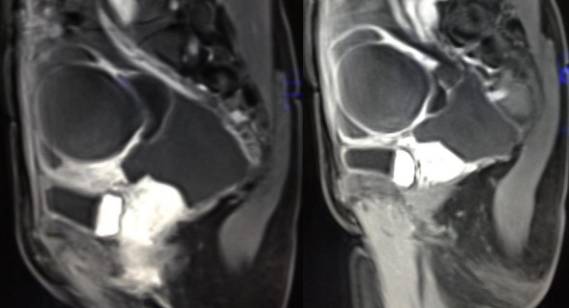

病理结果:黄体血肿

黄体血肿为正常排卵过程中,卵泡层破裂,引起出血,较多的血液潴留在卵泡或黄体腔内形成血肿。

正常黄体直径为15mm左右,以后转变为白体,并在下一个周期的卵泡期自然消退。若黄体内出血量较多,则形成黄体血肿,或称黄体内出血,出血性黄体。黄体血肿多为单侧,一般直径为40mm,偶可达100mm,黄体血肿被吸收后可导致黄体囊肿,较大的血肿破裂时可出现腹腔内出血,剧烈腹痛、少量阴道流血和腹膜刺激征,不易与宫外孕区别。

黄体血肿早期:囊内出血较多时,表现为卵巢内近圆形囊肿,囊壁厚,内壁粗糙。

黄体血肿中期:黄体血肿内血液凝固,部分吸收,囊壁变薄而,内壁光滑。

黄体血肿晚期:血液吸收后囊肿变小,转变为白体,内部回声呈实性稍高回

声,与周围卵巢组织分界不清,面靠彩超显示其周围环状血流判断,当血液完全吸收后形成黄体囊肿,囊壁变得光滑,与卵巢其他囊肿难以区分。

根据时间不同MR信号也有所不同,TIWI脂肪抑制序列可以鉴别脂肪和出血。